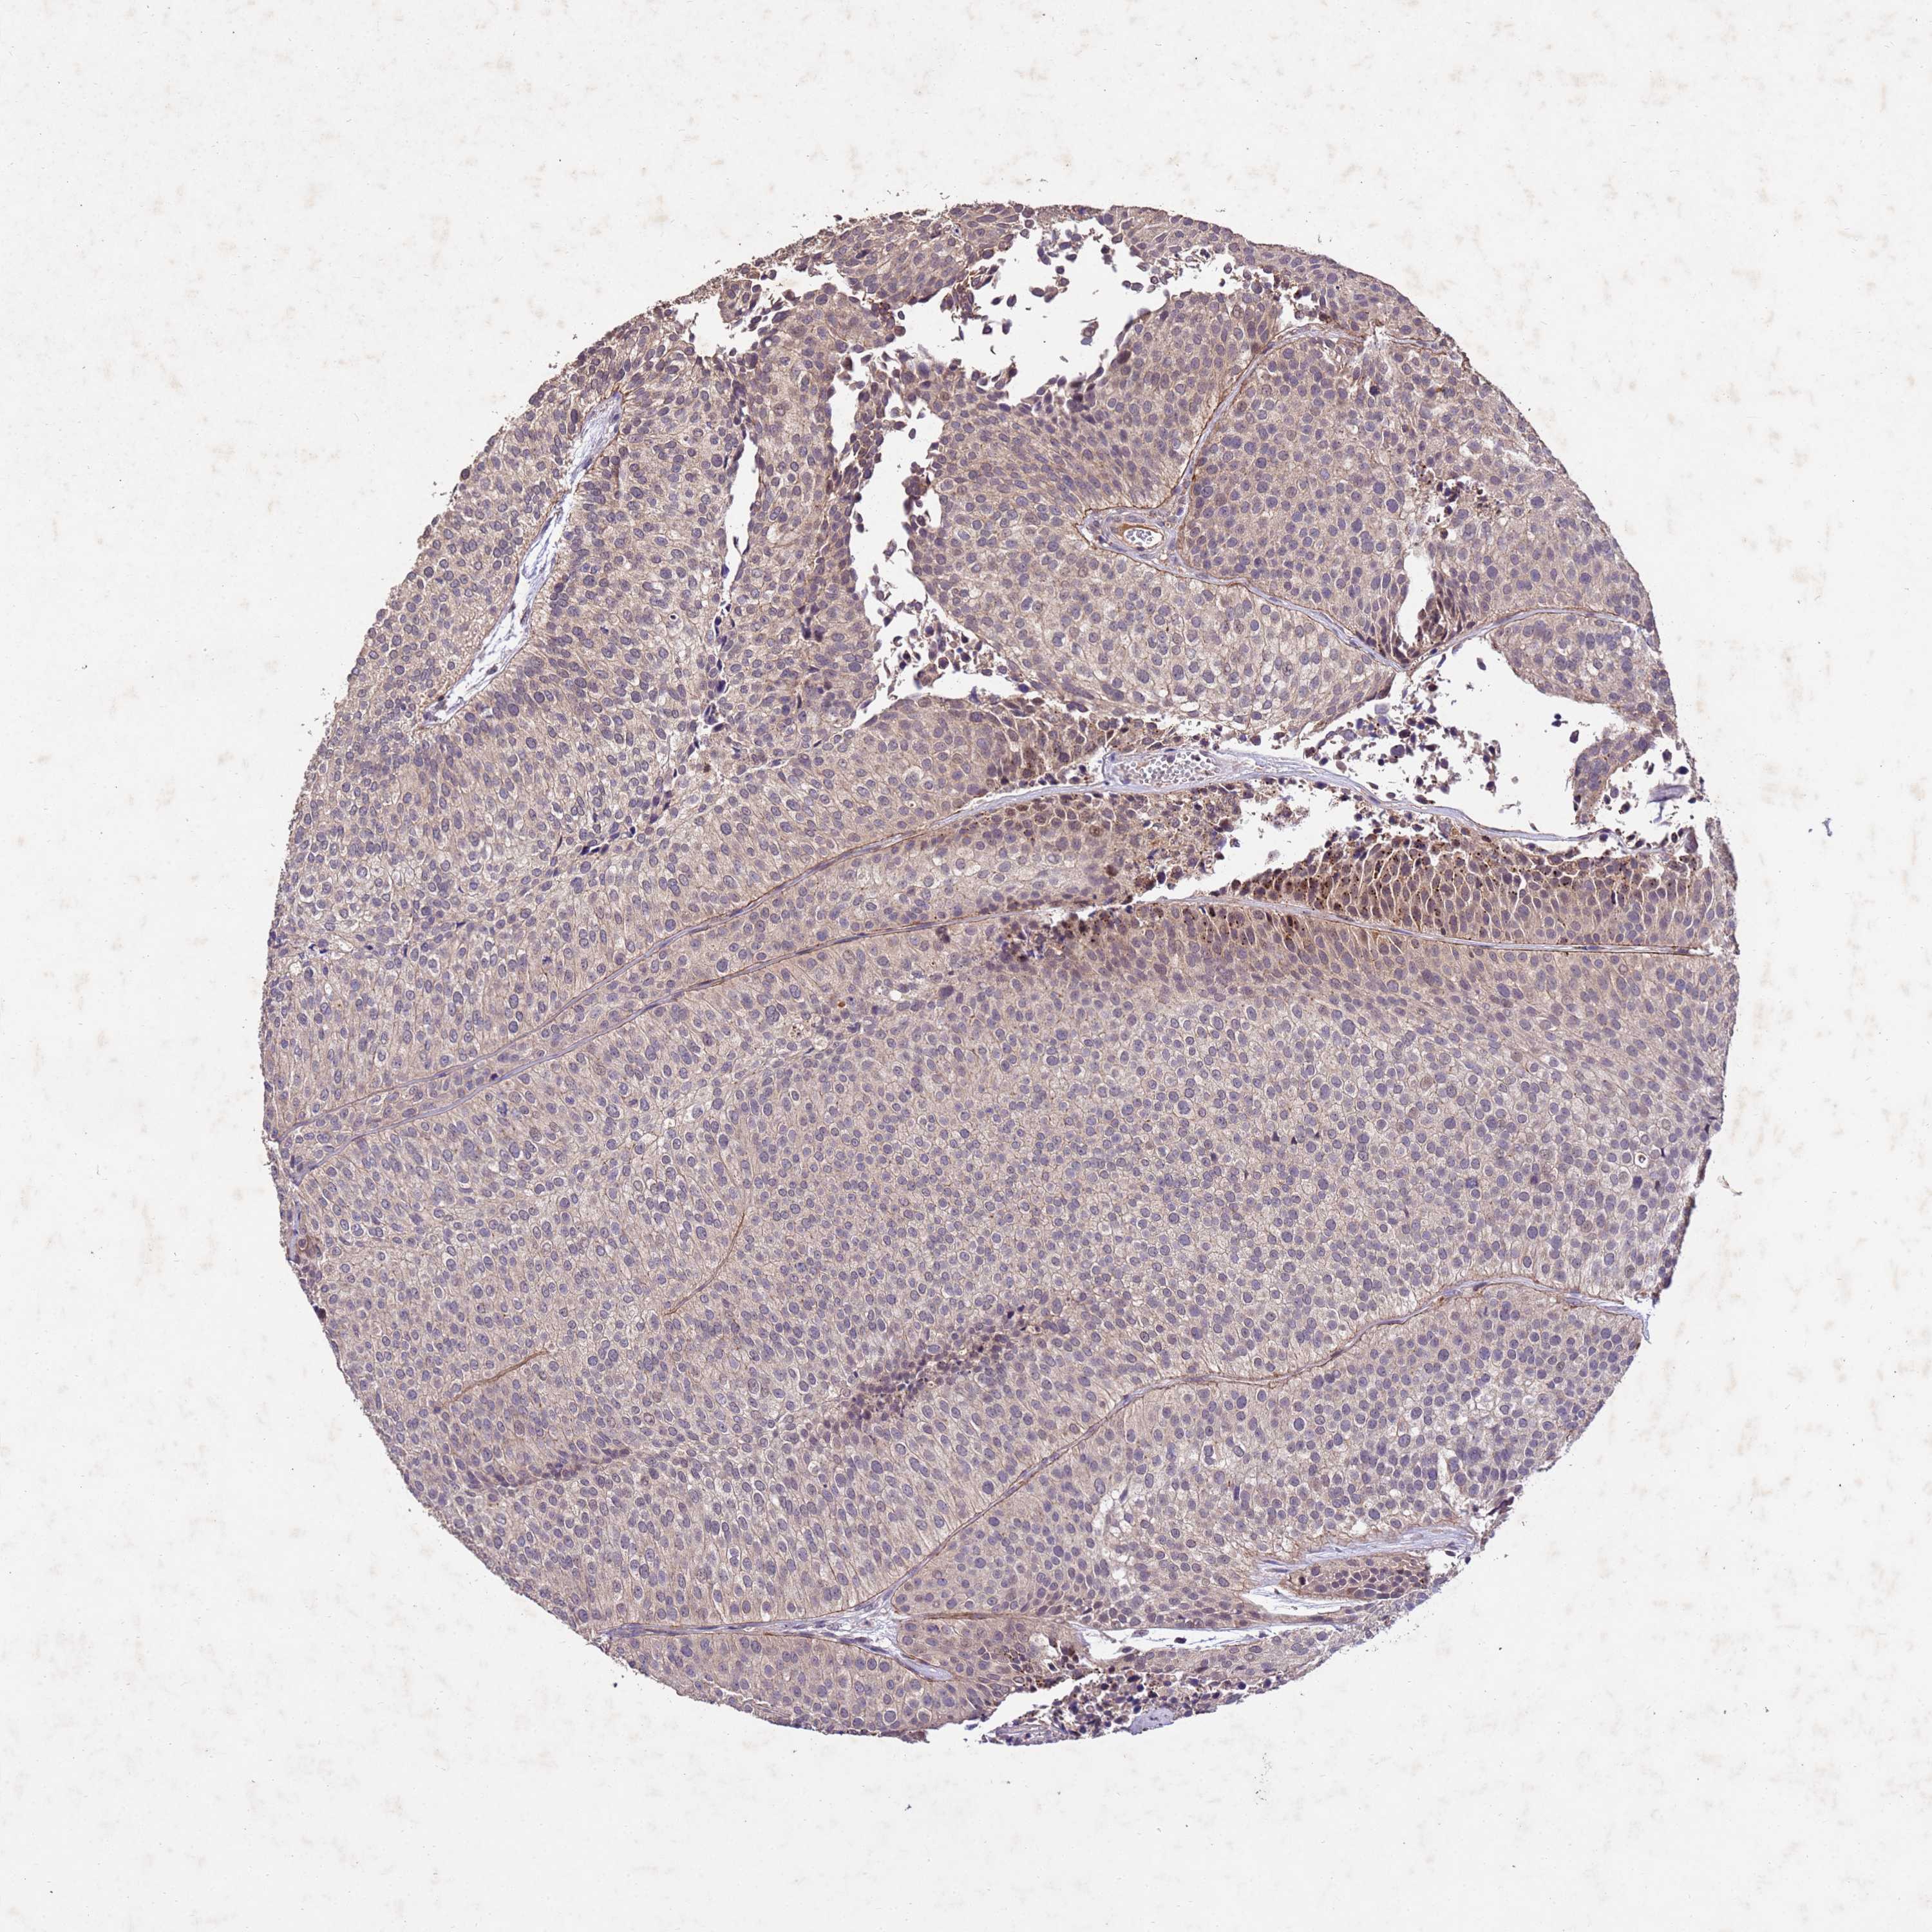

UROTHELIAL CANCER - Protein expressioni

A mouse-over function shows sample information and annotation data. Click on an image to view it in a full screen mode. Samples can be filtered based on level of antibody staining by selecting one or several of the following categories: high, medium, low and not detected. The assay and annotation is described here.

Antibody stainingi

Antibody staining in the annotated cell types in the current human tissue is reported as not detected, low, medium, or high, based on conventional immunohistochemistry profiling in selected tissues. This score is based on the combination of the staining intensity and fraction of stained cells.

Each image is clickable and will lead to virtual microscopy that enables deeper exploration of all samples and also displays staining intensity scores, fraction scores and subcellular localization as well as patient and tissue information for each sample.

Antibody HPA044913

Staining

High

Medium

Low

Not detected

Intensity

Strong

Moderate

Weak

Negative

Quantity

>75%

75%-25%

<25%

None

Location

Nuclear

Cytoplasmic/membranous

Cytoplasmic/membranous,nuclear

Urothelial carcinoma, Low grade

Urothelial carcinoma, High grade

Urothelial carcinoma, NOS